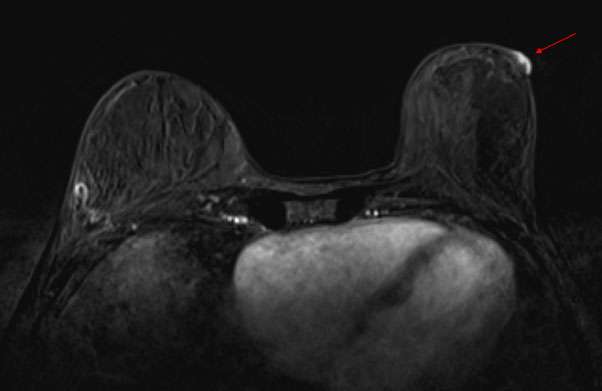

Case: Paget's Disease Figure 3

Figure 3: Contrast enhanced breast MRI demonstrates abnormal enhancement of the left nipple and areola, consistent with biopsy-proven Paget’s disease of the breast.